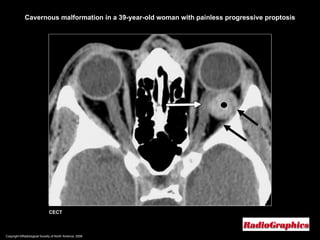

Copyright ©Radiological Society of North America, 2008 CECT Cavernous malformation in a 39-year-old woman with painless progressive proptosis

Cavernous Hemangioma CT and MR imaging; May be located anywhere in the orbit but frequently (83%) occur within the retrobulbar muscle cone. Uncommonly, an intramuscular hemangioma may occur. Well-defined masses.  Variable contrast enhancement.  Always respect the contour of the globe ( until ruptured ).  Orbital bone modeling is not uncommon.

Cavernous Hemangioma M/C orbital vascular tumor in adults. Most often in women (60%–70%) between the ages of mean age, 43–48 years. Slowly progressive enlargement.  Histologically, composed of large, dilated vascular channels (sinusoid-like spaces) lined by thin, attenuated endothelial cells. A distinct fibrous pseudocapsule.